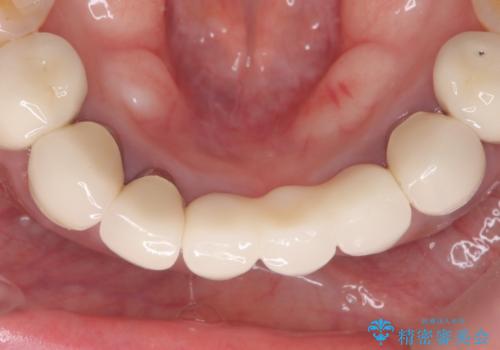

前歯が一本取れた オールセラミックブリッジによる補綴治療

抜歯をしているため、その部位の治癒を待ってからブリッジを装着するので、2-3か月ほど治療期間を必要としました。